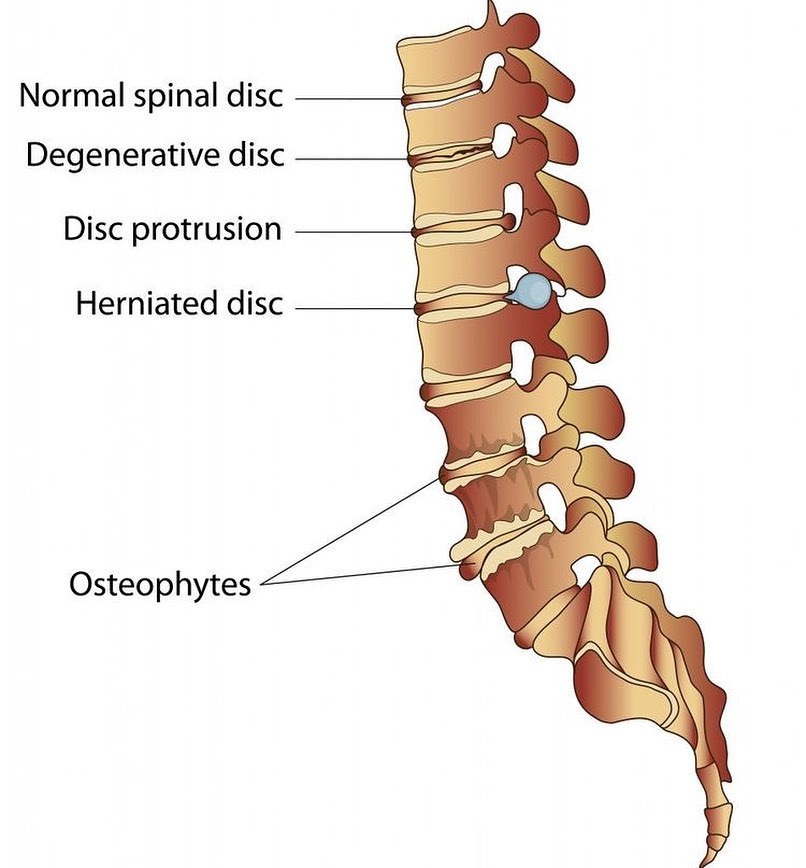

#Spinaldisc pathology can cause leg and/or #backpain -if you're suffering call us for a consultation 0207 935 4750

As we age, our spinal discs degenerate, which may cause the disc to lose its height or bulge out—potentially compressing a nerve, causing pain or other symptoms. Learn more about spinal discs at rediscovermylife.org/anatomy.php. #rediscover #centinelspine #spinaldisc #discbulge

Treating A Degenerated Spinal Disc Symptoms of degenerative disc disease include pain, paresthesia, and weakness. Spinal fusion surgery is used when symptoms worsen. #spinaldisc #degeneration #mvscburnsville zurl.co/hr68

#Spinaldisc pathology can cause leg and/or #backpain -if you're suffering call us for a consultation 0207 935 4750

know your disc problems. total spine could help you recover from every kind of disc problems. . . . #spinaldisc #spine #backpain #neckpain #wellness #healthylifestyle #scoliosis #pain #spinehealth #posture #painrelief #doctor #surgery #cancer #orthopedics #kneepain #spinesurgeon

Herniated disc, bulging disc ... what's the difference? Here's a list of these common terms and what they really mean #spinaldisc #discpain #spinalhealth bit.ly/2sncRjj